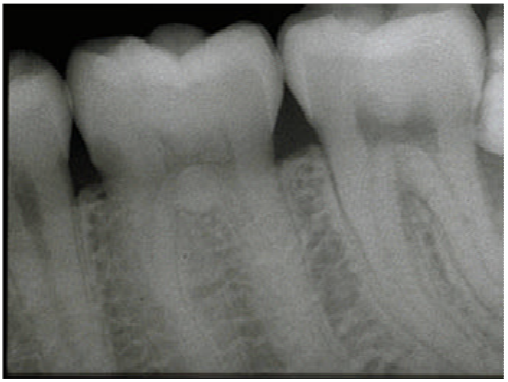

65.下圖根尖X光片中,白色箭頭所指為何構造?

(A)Periodontal ligament space (B)Alveolar crest (C)Cementum (D)Lamina dura